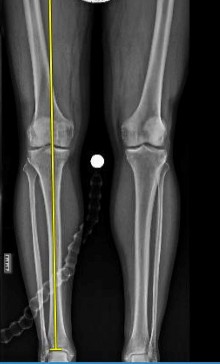

An otherwise healthy 31-year-old man has had right knee pain for the past 9 months. His former physician

administered a cortisone injection and ordered 6 months of physical therapy. The patient later had an arthroscopy with debridement of the right knee by another physician and completed another course of physical therapy. The patient received minimal relief from these treatments and still is not able to walk longer distances or go on hikes. On examination, he is a healthy appearing male with a body mass index of 24 kg/m2. He has a small effusion, minimal quadriceps atrophy, no tenderness about the knee, full range of motion, stable to varus and valgus stress at 30° of flexion, a grade 1 Lachman test, and a normal posterior drawer. Figures 1 through 4 are his arthroscopic views, radiograph and MRI scan from his prior surgical procedure. What is the next most appropriate step in treatment?